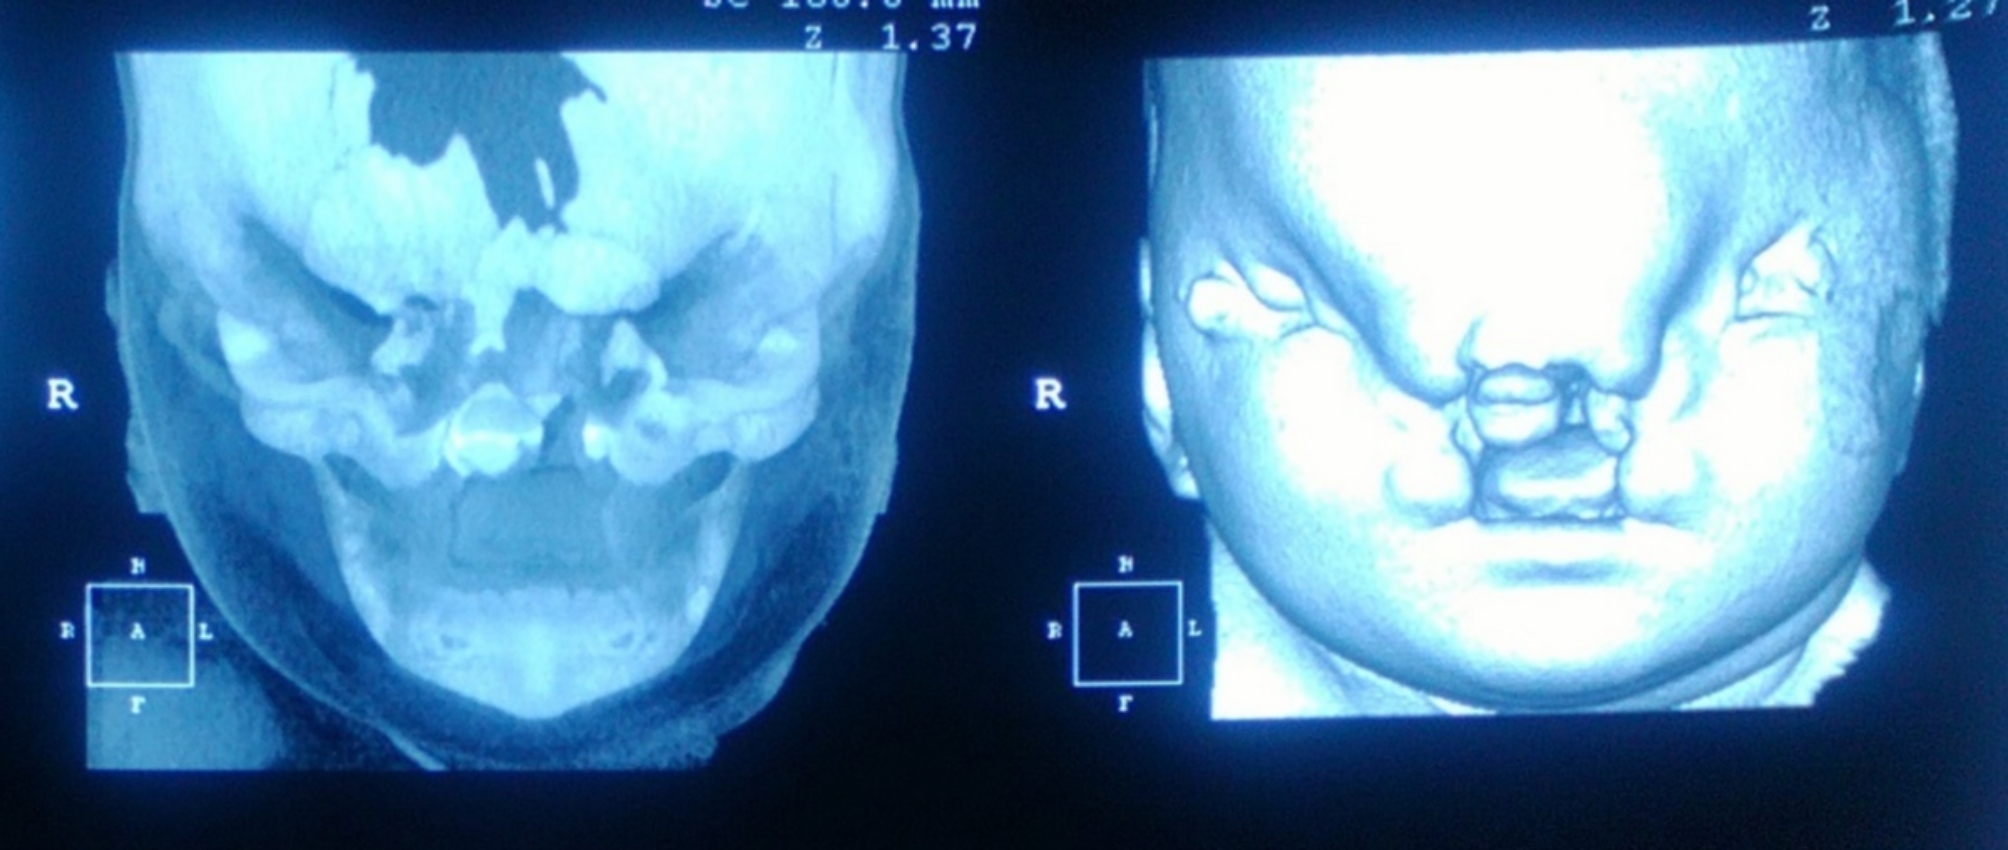

Bayi yang dilahirkan mengalami pelbagai jenis kecacatan di bahagian muka

Pada minggu ke-37 kehamilan, dia akhirnya selamat melahirkan bayi tersebut melalui prosedur caesarean (czer). Namun begitu, bayi itu hanya mempunyai berat sekitar 2.45kg, jauh lebih rendah daripada purata berat bayi baru lahir yang normal. Lebih menyedihkan lagi, si kecil itu turut mengalami Frontonasal Dysplasia iaitu keadaan di mana proses embriogenesis muka mengalami kecacatan.

Akibat daripada itu, matanya disahkan buta, rambut kulit kepala jarang, penonjolan dahi, batang hidung mendap, bibir dan lelangit sumbing yang melibat seluruh kawasan mulut. Posisinya telinga turut berada dalam keadaan terpusing ke belakang selain alat kelamin lebih besar daripada kebiasaan.